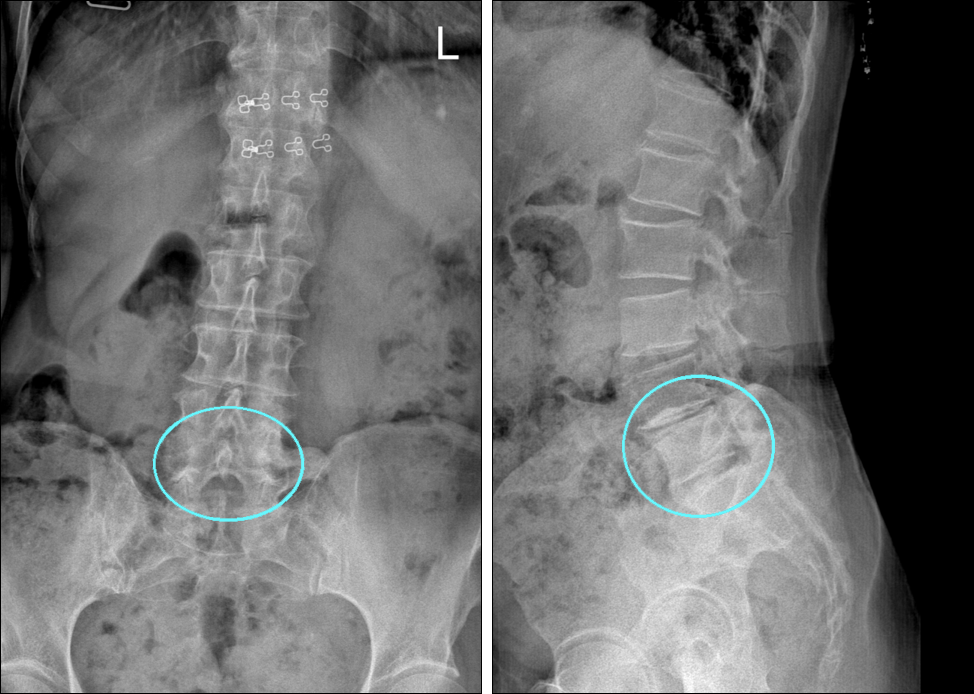

과거 허리통증으로 주사치료를 받았으나 악화되어 종아리 통증, 발바닥 시림까지 발생한 환자.

요추 4-5번, 요추 5-천추 1번 간격이 좁아지고

추간판 높이도 감소, 후관절이 두꺼워지고 골극도 자란 상태